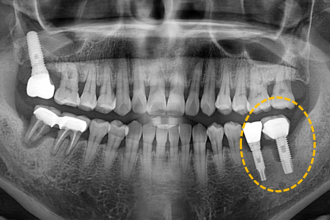

임플란트